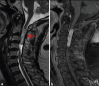

Schwannomas are benign soft-tissue tumors that arise from peripheral nerve sheaths throughout the body and are commonly encountered in patients with neurofibromatosis Type 2. The vast majority of schwannomas are benign, with rare cases of malignant transformation reported. In this pictorial review, we discuss the magnetic resonance imaging (MRI) appearance of schwannomas by demonstrating a collection of tumors from different parts of the body that exhibit similar MRI characteristics. We review strategies to distinguish schwannomas from malignant soft-tissue tumors while exploring the anatomic and histologic origins of these tumors to discuss how this correlates with their imaging findings. Familiarity with the MRI appearance of schwannomas can help aid in the differential diagnosis of soft-tissue masses, especially in unexpected locations.